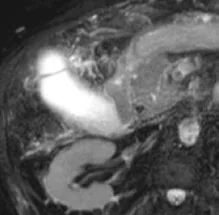

Figure 2.

A. Acquisition 3D de bili-IRM. Chez ce patient à la respiration irrégulière, l’échec de la synchronisation respiratoire (nécessaire à l’acquisition de cette séquence) rend dans ce cas les images quasi ininterprétables.

B. Ici, c’est une coupe épaisse 2D acquise lors d’une courte apnée qui s’avère plus contributive pour montrer l’empierrement cholédocien (têtes de flèches)